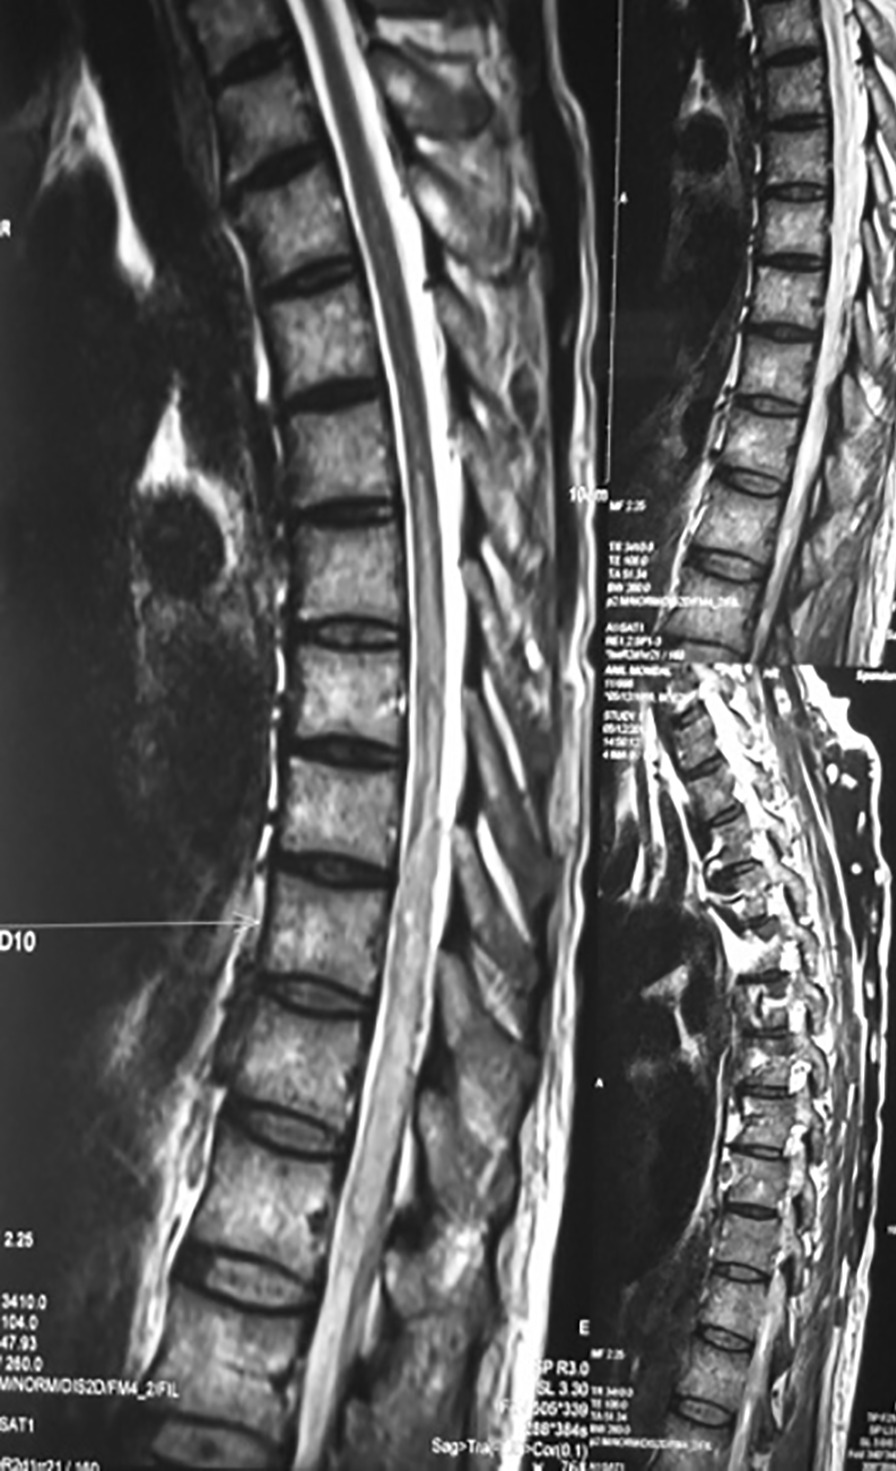

Fig. 2.

Magnetic Resonance Imaging of dorsal spine (plain and contrast) showing diffuse cord swelling with edema in the lower dorsal spinal cord extending up to conus medullaris accompanied by patchy enhancement within. Extensive neurocysticercosis within both paravertebral as well as posterior paraspinal muscles is visible. (Arrow shows the position of 10th thoracic vertebra)